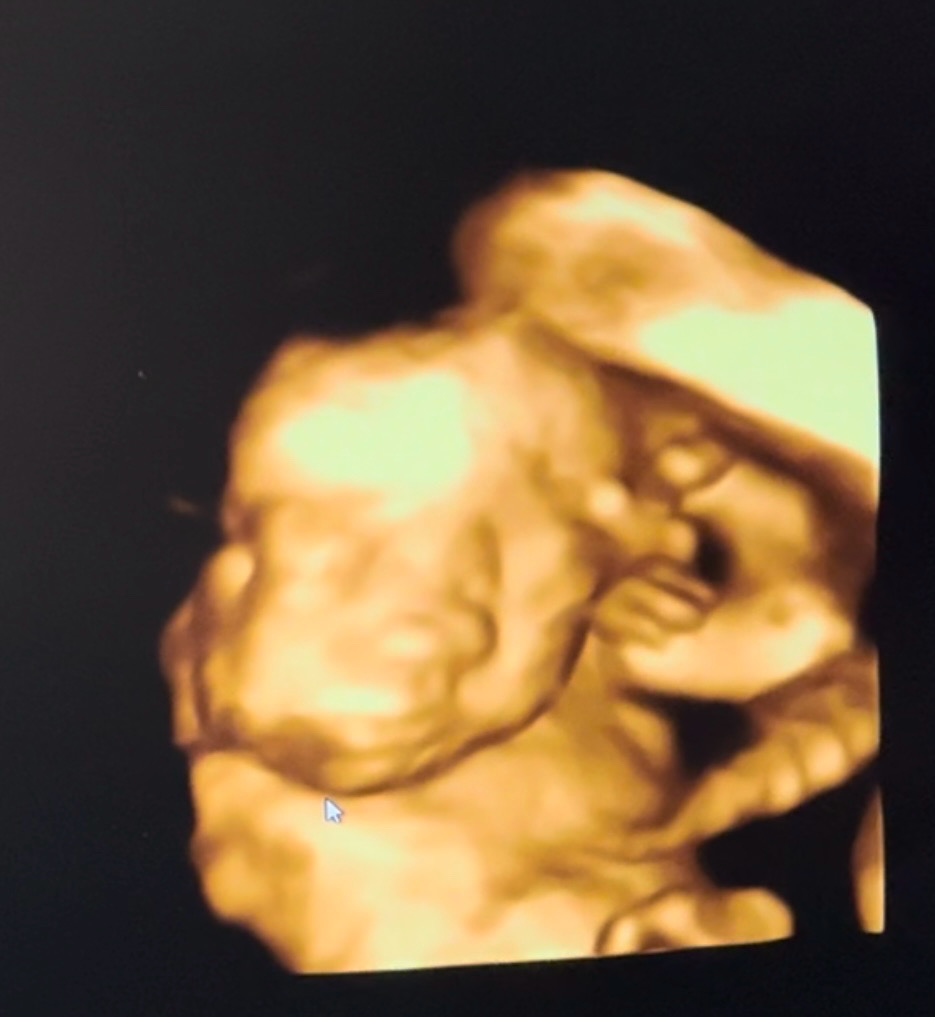

検診待ちきれず違う病院に4dしにいってしまった……笑笑 23w4dのエコーです! 今回は動画も撮って貰ったけど可愛い…… 毎回愛しさ増し増し 本当に早く産みたい会いたい 産まれたら大変なこと増えるけど それでもいいから早く会いたいーーー!!!

動画だと可愛さもさらに増しますよね🥺

動画だと本当に可愛いです🥺